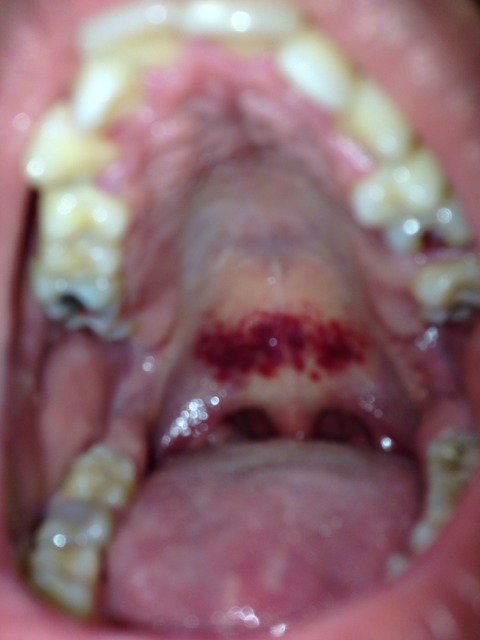

Tache De Sang Sur Palais Douleur Forum Sante